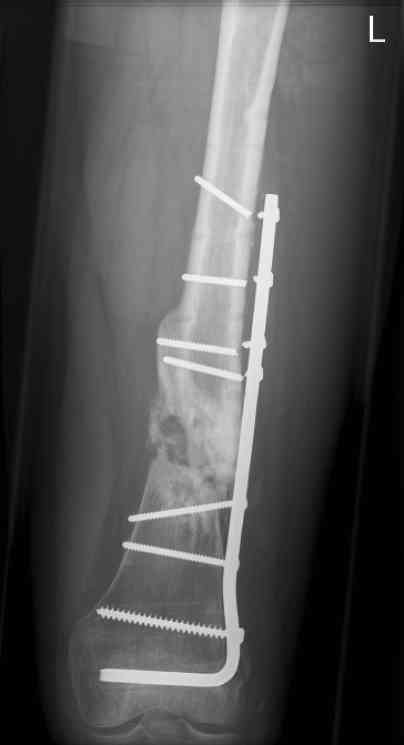

16 yr old boy, high energy motorcycle trauma trauma in July 2005 with:

- hip dislocation + acetabular fracture L

- distal femoral fracture L

- tibial shaft fracture L

- metatarsal fractures L

july 05: LISS femur, LCP plate tibia, double recon. plate post. acetabulum

oct 05: cancellous bone graft femur

aug 06: blade plate + bone graft

nov 06: revision blade plate

feb 07: retrograde nail + bone graft + BMP

may 07: dynamisation nail

sept 07: locking screw removal (max. dynamisation reached)

nov 07: persistant non-union distal femur; other fractures healed uneventfully.

All with gradual/partial weightbearing etc. Currently 50-100% weight bearing, no pain.

Soft tissues are intact. No smoking or diabetes.CRP <2